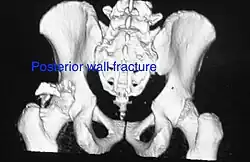

-

Posterior wall fracture as seen on 3-D CT scan -

| Posterior wall | This is the most common variety of acetabular fracture. It typically occurs due to dashboard injury; when a person travelling in a vehicle involved in a head-on collision, the force applied over the flexed knee travels along the femur bone to the head of the femur, breaking the posterior wall of the acetabulum. The head of the femur is dislocated outside the joint. | T shape | When a transverse fracture also had a vertical fracture line, it is called a T shape fracture. Here the innominate bone is broken in such a way that all three parts of it, the ilium, the ischium and the pubis are separated from one another. This is a three part fracture. Though both columns are broken, the weight bearing dome is still attached to the main part of the ilium and hence it is not a true fracture of both columns.